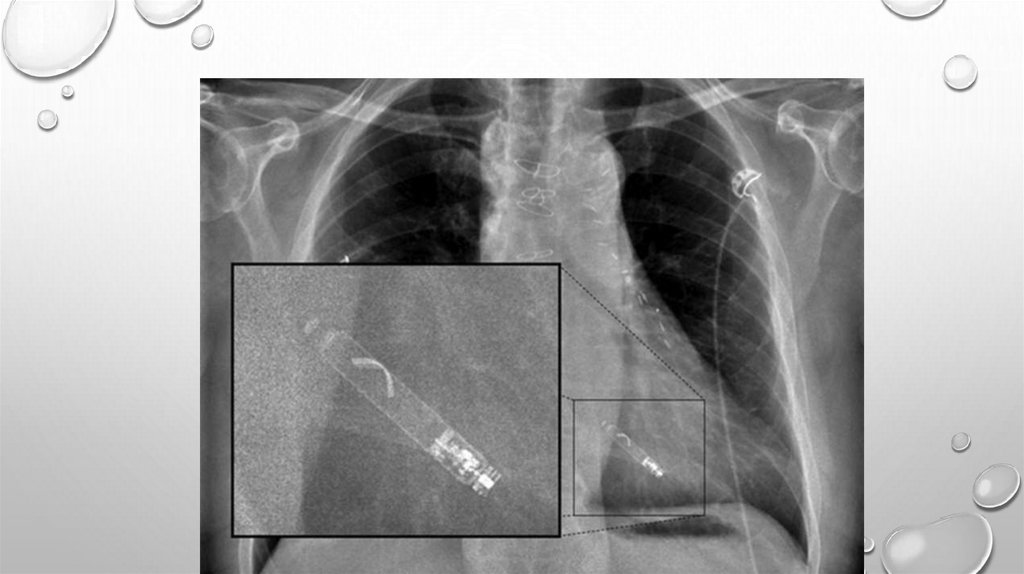

СИСТЕМА ИМПЛАНТАЦИИ